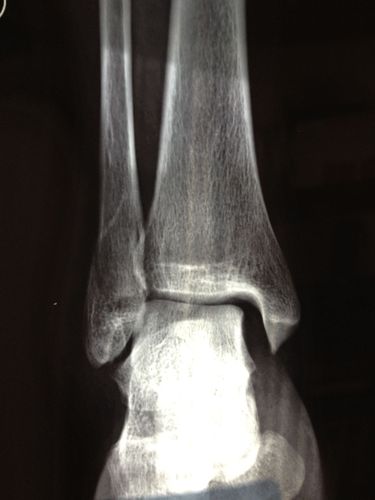

外踝扭伤了,肯定要拍个踝关节正侧位片,看看有没有腓骨下端的骨折

右脚踝扭伤,腓骨骨折,关节移位.请看x光片,谢谢.